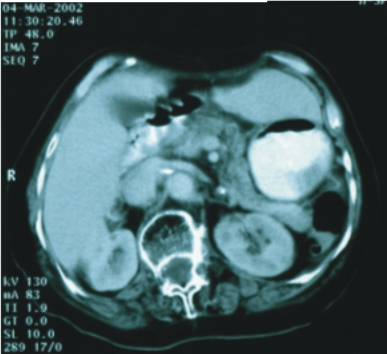

68歲/女性 (胰臟癌,無法手術) |

67歲/女性 (胰臟頭癌) |

||

| 89/9/25 (治療前) |

90/3/4 (治療後) |

86/9/23 (治療前) |

90/11/13(治療後) |